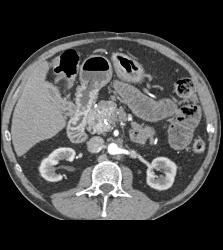

1cm Islet Cell Tumor of the Pancreatic Head With Liver Lesion- See Full Sequence